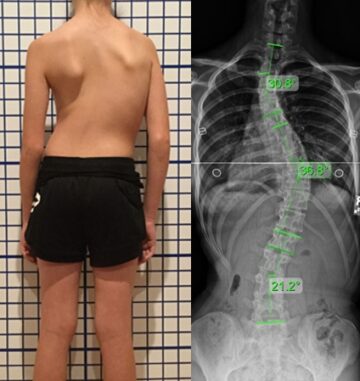

اعوجاج العمود الفقري : الأسباب، الأعراض، التشخيص والعلاج اعوجاج العمود الفقري هو انحناء جانبي غير طبيعي في العمود الفقري، بحيث يظهر العمود الفقري بشكل حرف (S) أو حرف (C) بدلًا من أن يكون مستقيمًا

اعوجاج العمود الفقري عند الأطفال | الأسباب، الأعراض، وطرق العلاج المبكر يُعد اعوجاج العمود الفقري (الجنف) من أكثر مشكلات العمود الفقري شيوعًا عند الأطفال والمراهقين. تشير الدراسات إلى أنه يصيب ما يقارب 3% من

اعوجاج العمود الفقري مجهول السبب عند المراهقين: دليلك للاكتشاف المبكر والعلاج الفعّال اعوجاج العمود الفقري مجهول السبب، المعروف طبيًا باسم الجنف مجهول السبب، هو انحناء جانبي غير طبيعي للعمود الفقري يظهر غالبًا خلال مرحلة